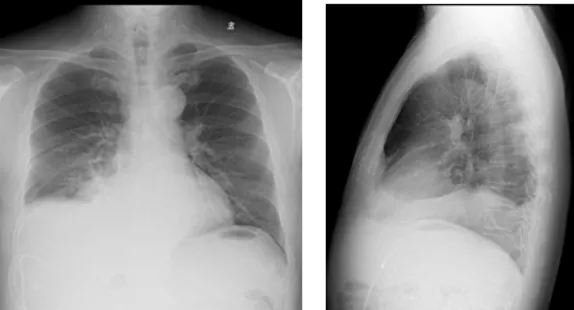

影像學(xué)檢查結(jié)果

右肺炎癥不能排除,請(qǐng)結(jié)合臨床。右側(cè)少量胸腔積液

右側(cè)胸腔積液細(xì)胞學(xué)檢查結(jié)果

(右側(cè)胸腔積液)細(xì)胞學(xué)檢查見(jiàn)少數(shù)惡性細(xì)胞,形態(tài)考慮腺癌細(xì)胞。